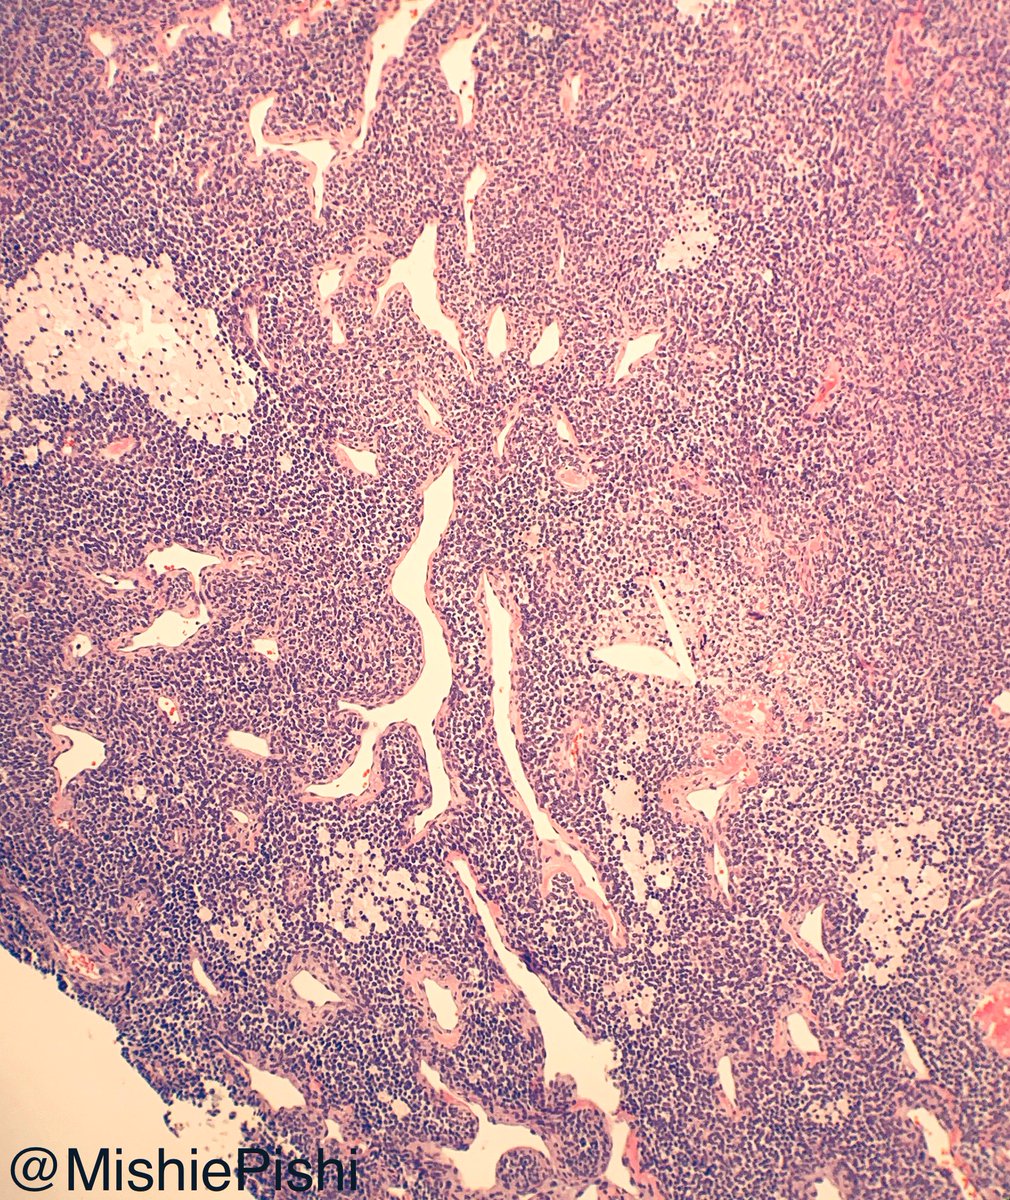

Nodular orbital mass in a child. What am I and what am I pathognomonic for? What are other clinical manifestations seen in these patients?

#pathology#PediPath#NeuroPathpic.twitter.com/NhzfliiVWW